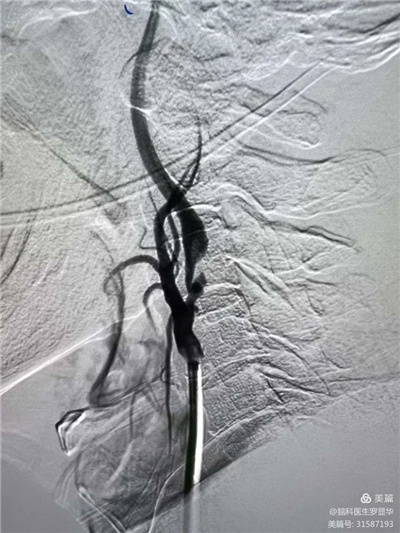

手術(shù)過(guò)程:指引導(dǎo)管到位

手術(shù)過(guò)程:球囊擴(kuò)張后,protege支架到位

術(shù)后造影示狹窄解除